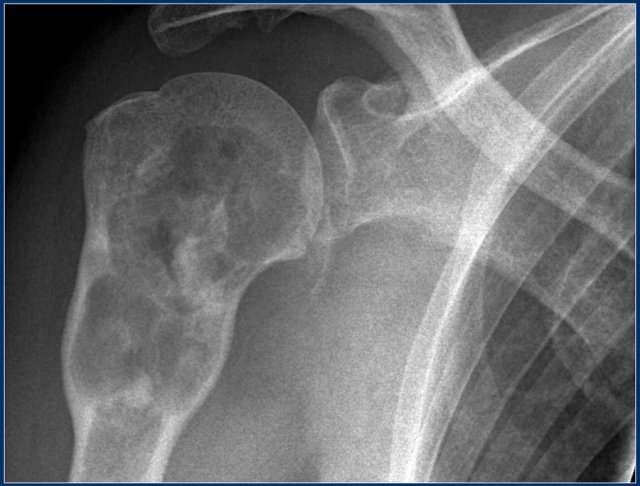

On the left a typical broad-based osteochondroma arising from the proximal humerus.

The major part of the bony protrusion consists of fatty bone marrow.

There is a thin peripheral cartilage cap, i.e. no suspicion for malignant degeneration.